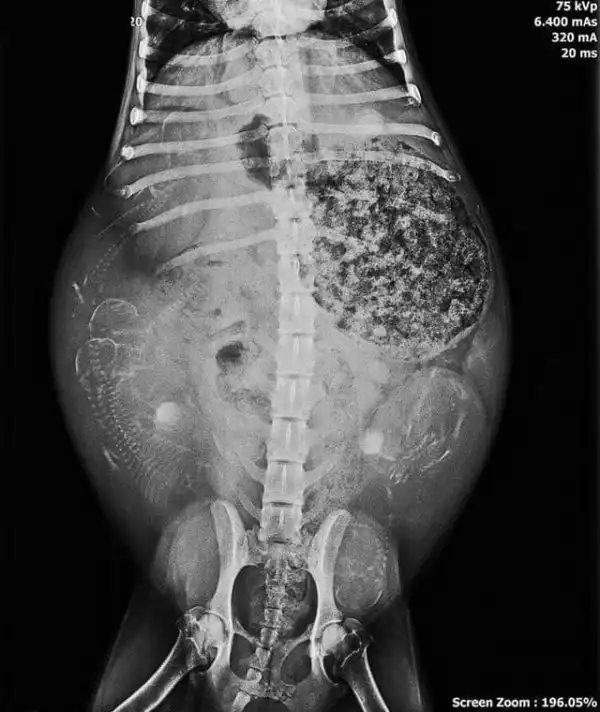

Рентген беременной собаки